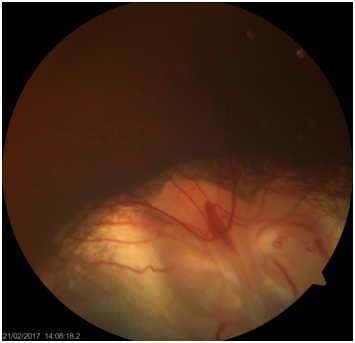

It is reported that the both retinal and choroidal vessels patterns are directly affected by the size and area of the coloboma (Figure 2).13

Figure 2 Involvement of optic disc in the coloboma.